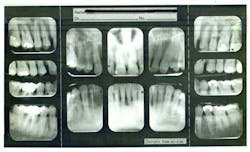

Figure 2: Full-mouth series

Because of my severe bone-loss condition (figures 2 and 2a), I was advised by many offices that my treatment should consist of: extraction, bone grafts, sinus lifts, implants, and crowns. This was very expensive and, I felt, very invasive. I was reluctant, preferring to try to keep my teeth.